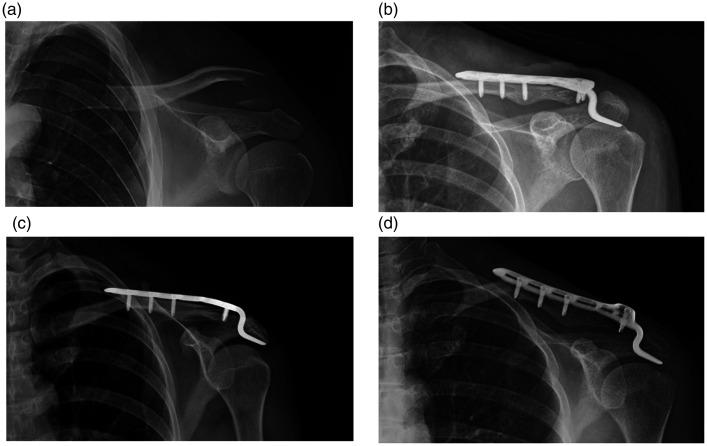

Neer type II fractures are common, and hook plate fixation is one of the recommended treatments. Although clavicular midshaft fractures after hook plate fixation are rare, such fractures increase patients' suffering and worsen their functional outcomes. This study was performed to identify the risk factors for this complication.

In both the complications group (n = 21) and control group (n = 331), significantly more patients of advanced age and significantly more patients treated with hook plates that were not bent during surgery developed midshaft fractures.

The risk of a clavicular midshaft fracture after hook plate fixation may be significantly increased by advanced age or a lack of hook plate bending.